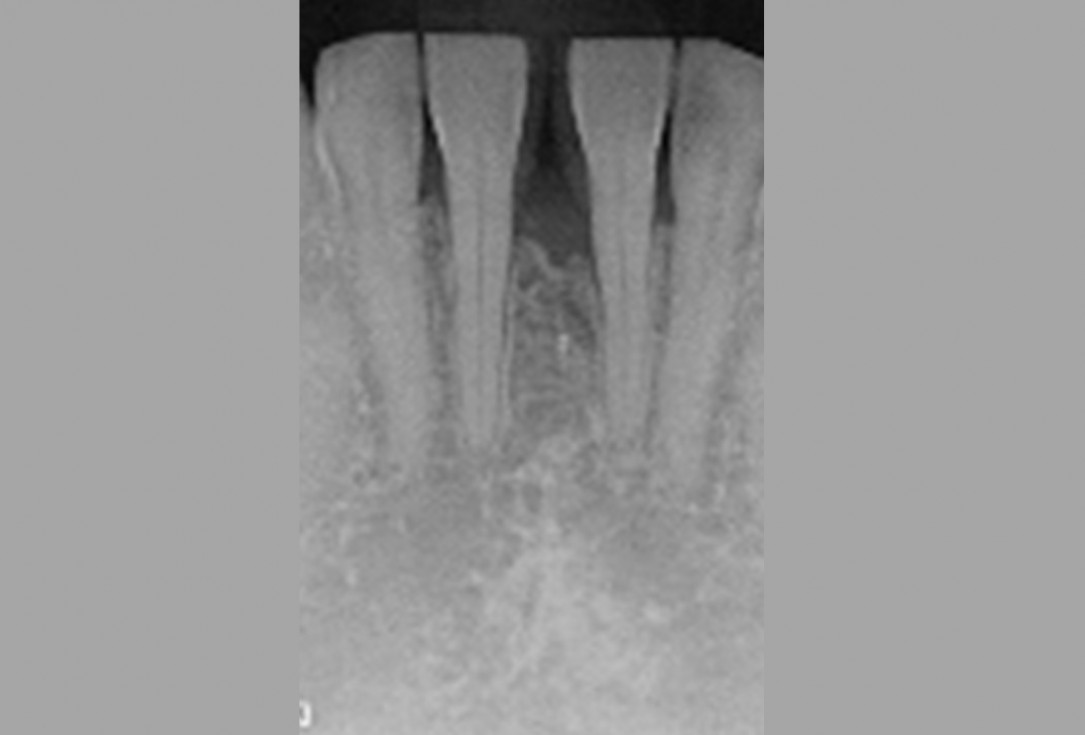

10/13 - Clinical situation 3 years post-operative.

Wide intrabony defect treated with the modified papilla preservation flap in conjunction with Straumann® Emdogain® and autogenous bone - Dr. B. Molnar